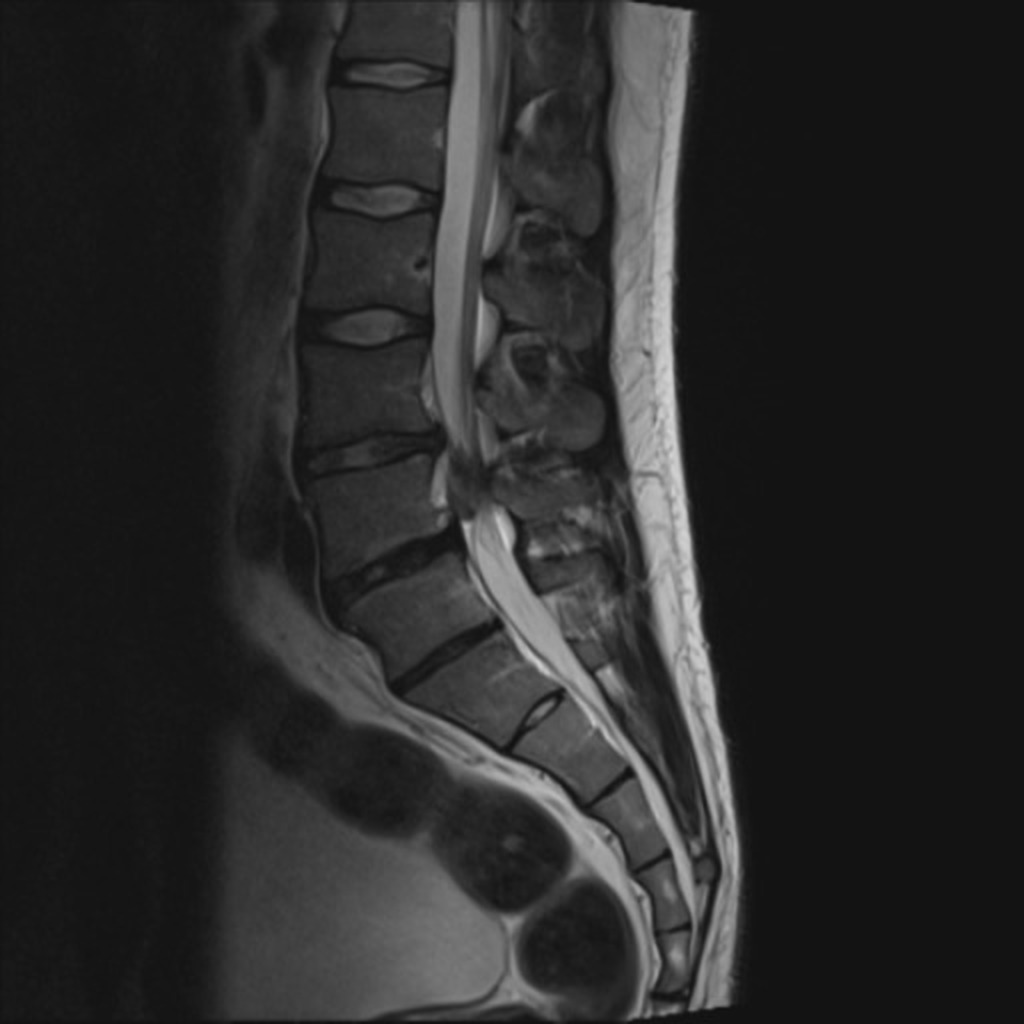

Lumbosacraal radiculair syndroom =

"Uitstralende pijn in één bil of been, al dan niet met andere prikkelingsverschijnselen en neurologische uitvalsverschijnselen, die suggestief is voor een prikkeling van één (of twee) specifieke lumbosacrale zenuwwortel(s)"2

Beeldvorming

• NHG (2015) NA 6 weken in samenspraak met patiënt2